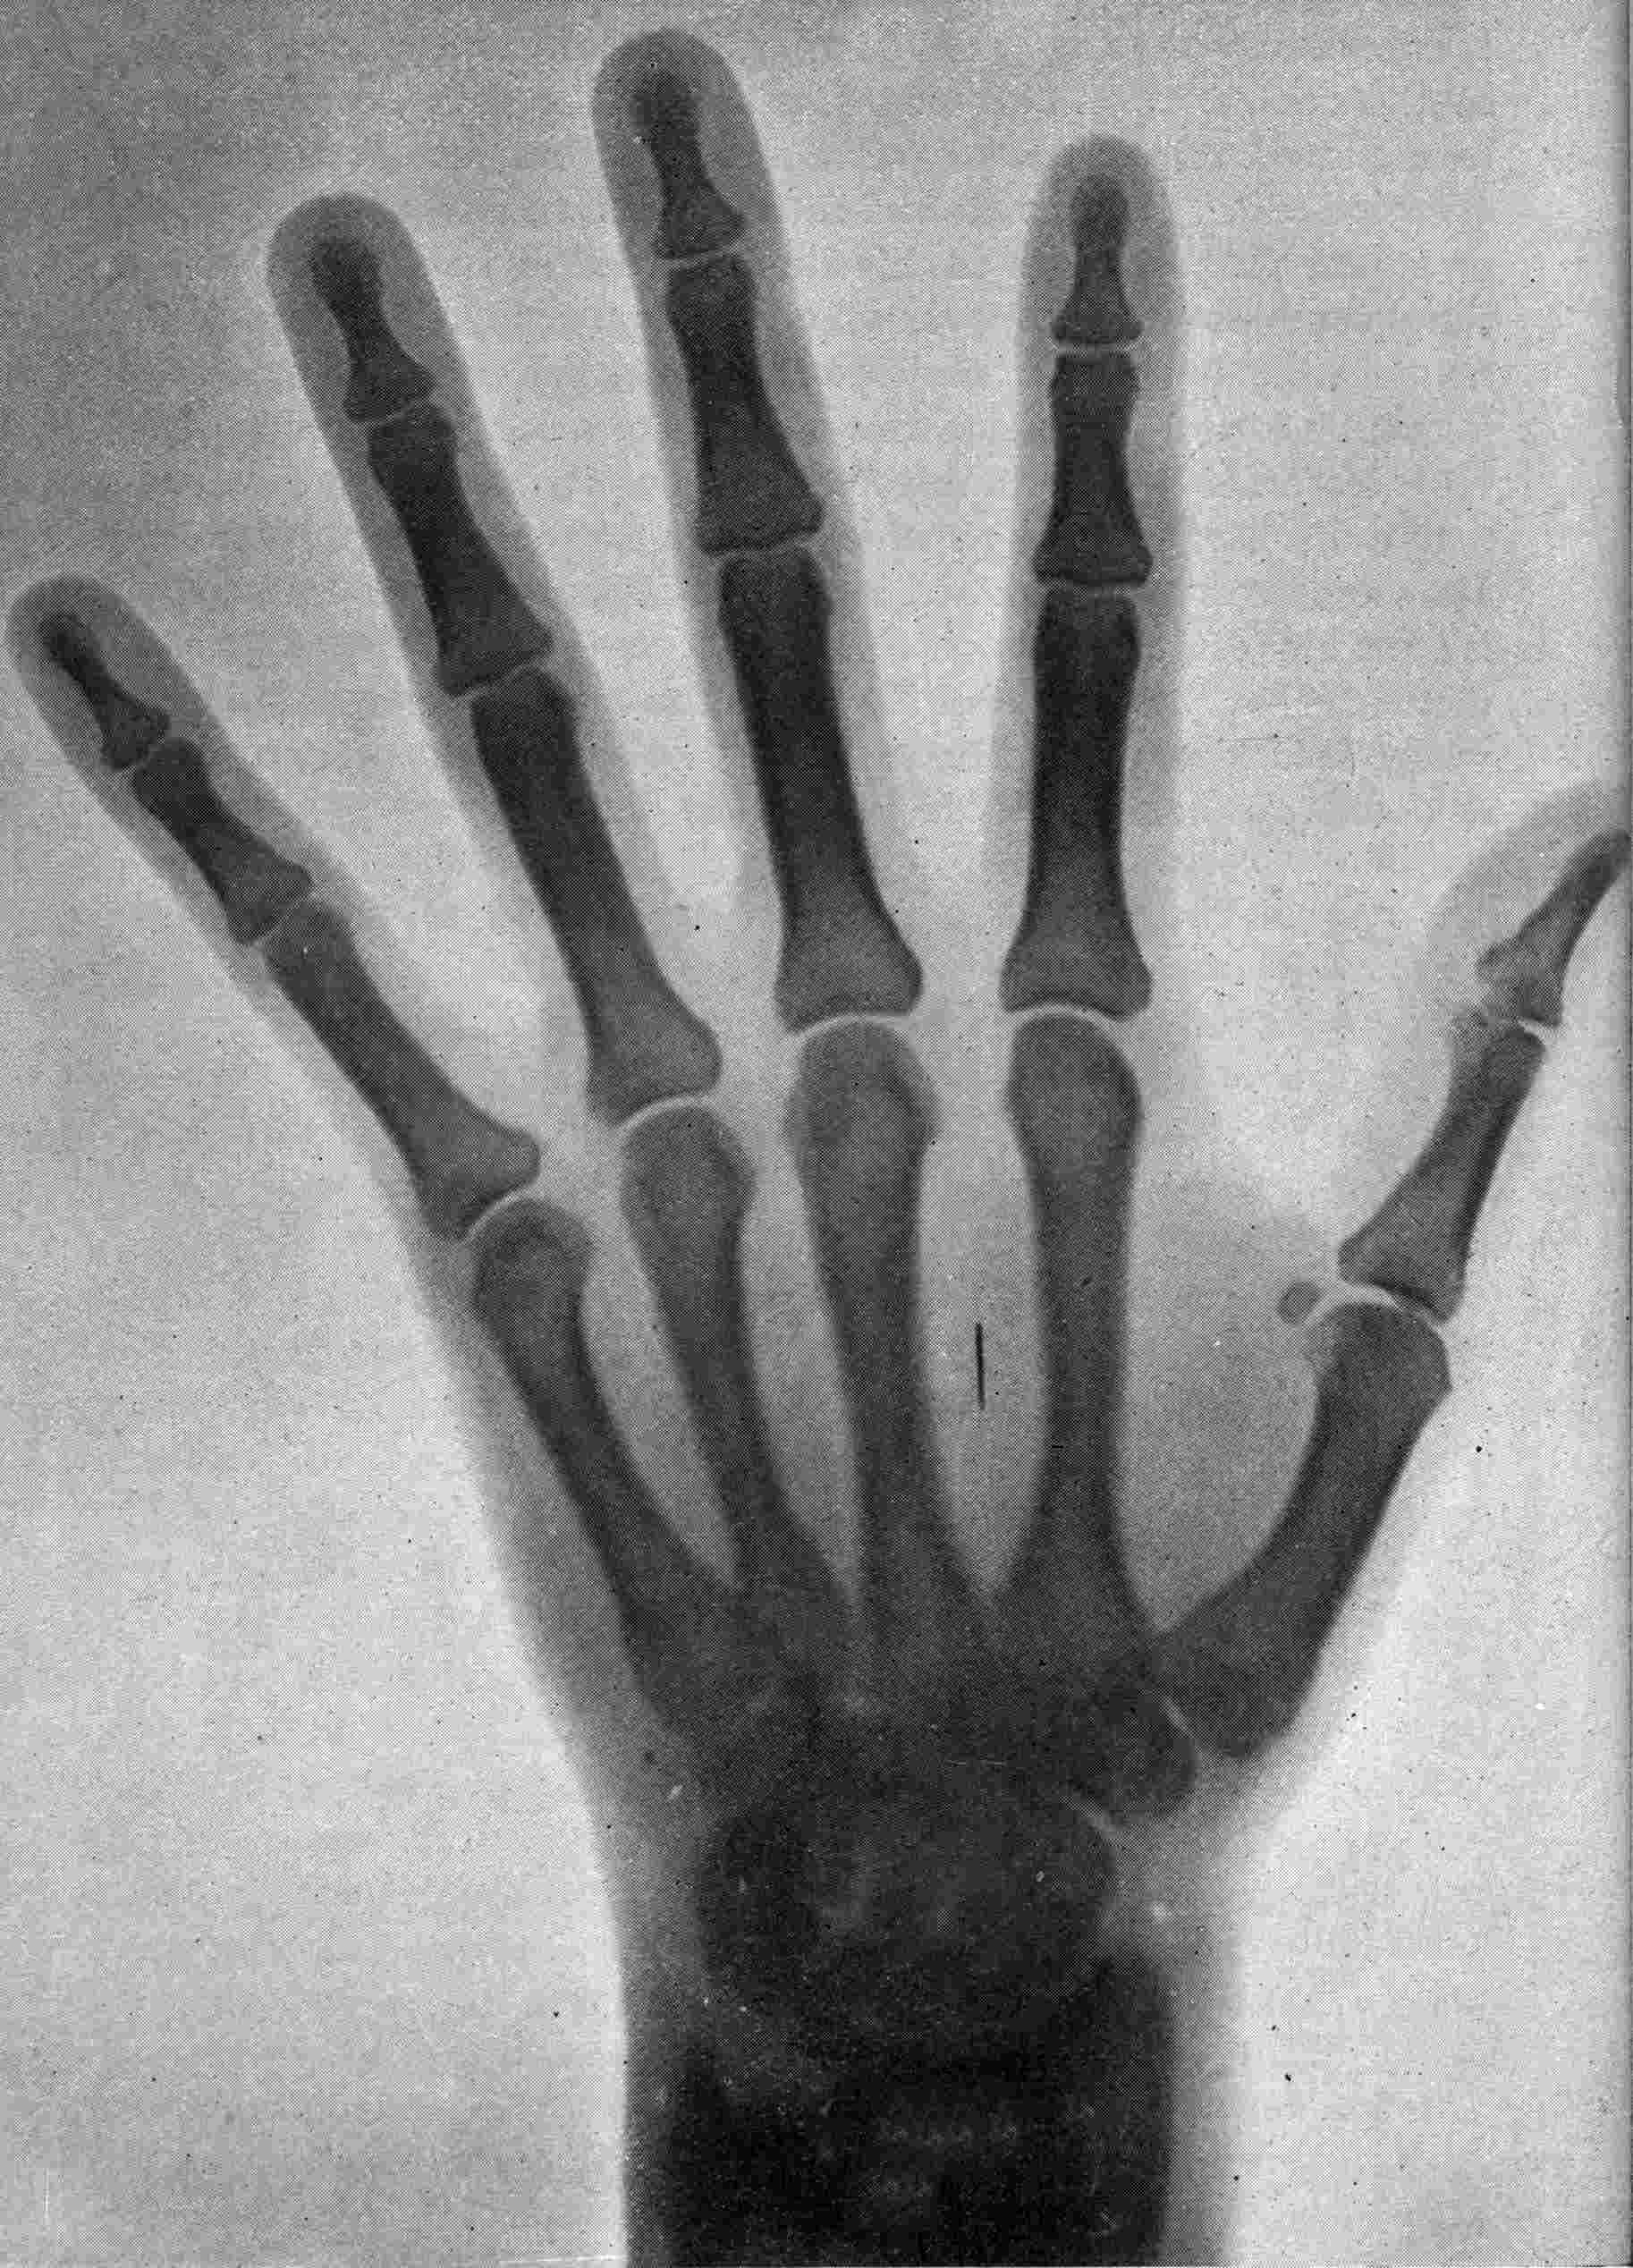

Fig. 2.—Broken Arm, Overlapping.

(Due to defective setting.)